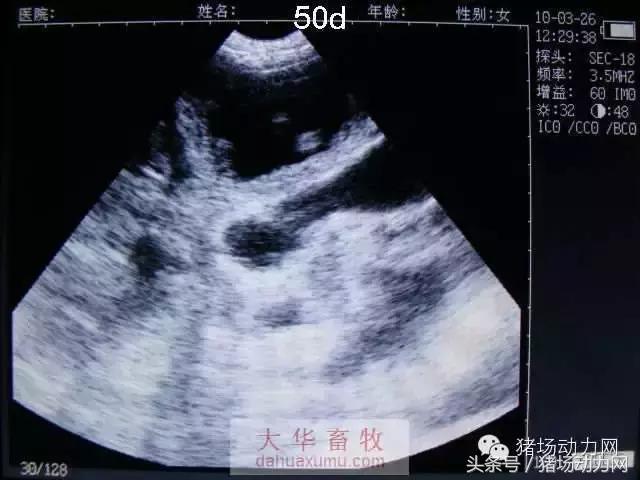

以下为怀孕母猪21天到90天之内的变化图:

50天